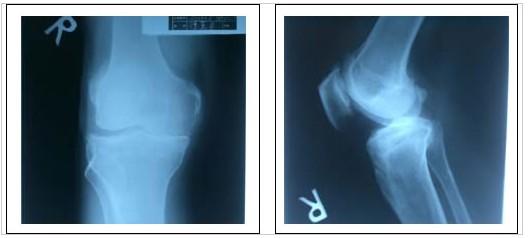

(3)关节间隙狭窄和骨性强直

持续的炎症导致滑膜不断增生,对关节软骨也会产生炎性损害。时间长了,增生物可出现钙化,和关节软骨破坏一起,导致关节间隙狭窄。在疾病的反复活动中,关节间隙狭窄也会逐渐增重,最终会使纤维化、钙化的增生物填充在两个关节面之间,造成关节骨性强直,完全丧失活动功能。

关节间隙狭窄